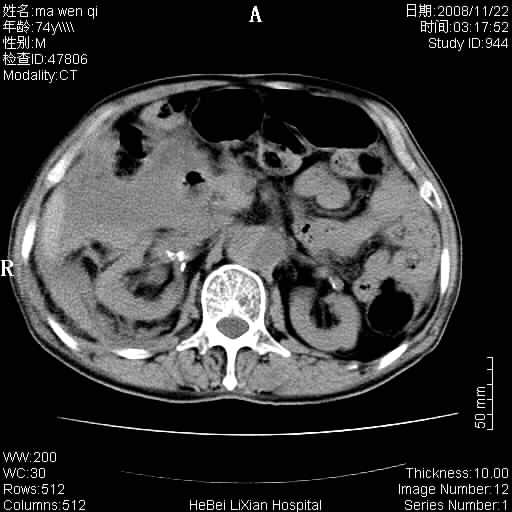

患者男 74岁.突然昏迷,休克6小时.血压70/30,头颅ct未见异常,既往体健.

补充病史,保留导尿10小时,尿袋内只有少许尿液,患者于住院后15小时后去世.

腹主动脉、双侧髂动脉夹层动脉瘤破裂出血进入腹腔。

1)考虑双侧髂动脉瘤并右侧动脉瘤破裂出血,右侧腹膜后及腹腔积血。2)双侧腹股沟疝。

1)考虑,腹主动脉、双侧髂动脉夹层动脉瘤破裂伴右侧腹膜后及腹腔积血。2)双侧腹股沟疝。

1)考虑胸、腹主动脉、双侧髂动脉瘤并右侧动脉瘤破裂出血,右侧腹膜后及腹腔积血。2)双侧腹股沟疝。